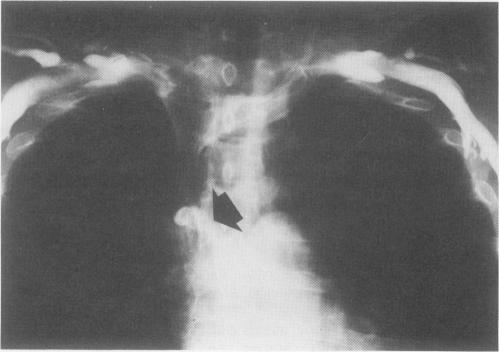

One hundred and forty patients with an intractable ascites complicating a chronic liver disease received a peritoneovenous shunt (PVS) using the LeVeen valve. Operative mortality was ten per cent but was 25% in patients with severe liver failure. Intraoperative drainage of ascites sharply decreased postoperative complications and mortality. One-year actuarial survival rate was 81.4%, respectively 77.7%, 61.3%, and 24.7% in patients with good liver function and moderate or severe liver failure. Variceal hemorrhage occurred in 11 patients and late infection in another 11 patients. Thirty-eight patients (30.5%) had recurrence of ascites. This was mostly due to an obstruction on the venous side of the shunt. An elective portacaval shunt had to be done in 23 patients for recurrence of ascites or variceal bleeding. Among the 57 patients still alive at time of writing, 51 were free of ascites. These results suggest that PVS is an efficient operation. This procedure may be largely indicated in the selected and small group of cirrhotic patients with true intractable ascites and moderate or no liver insufficiency.

140例伴有慢性肝病难治性腹水的患者接受了使用LeVeen瓣膜的腹腔静脉分流术(PVS)。手术死亡率为10%,但在严重肝功能衰竭患者中为25%。术中腹水引流显著降低了术后并发症和死亡率。肝功能良好以及中度或重度肝功能衰竭患者的1年精算生存率分别为81.4%、77.7%、61.3%和24.7%。11例患者发生静脉曲张出血,另有11例患者发生晚期感染。38例患者(30.5%)腹水复发。这主要是由于分流静脉侧梗阻。23例患者因腹水复发或静脉曲张出血不得不进行择期门腔分流术。在撰写本文时仍存活的57例患者中,51例无腹水。这些结果表明PVS是一种有效的手术。该手术在选定的一小群真正患有难治性腹水且肝功能中度不全或无肝功能不全的肝硬化患者中可能有很大的应用指征。